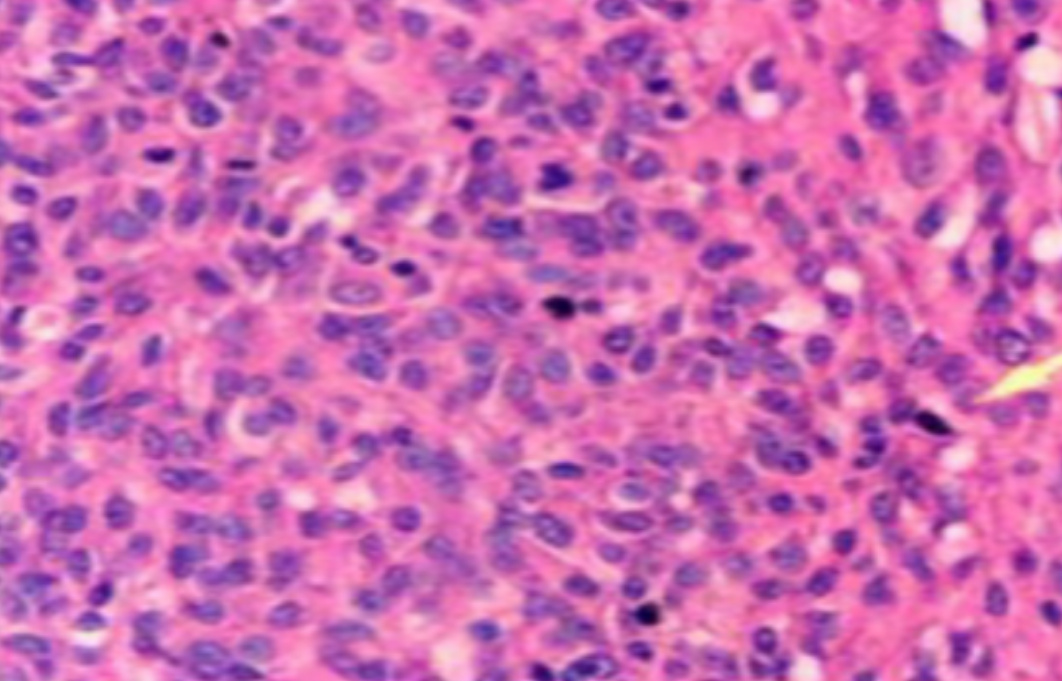

HE染色,全称苏木精-伊红染色法(Hematoxylin and Eosin staining),是最常见的组织切片染色技术之一,用于在显微镜下观察和分析组织或细胞的结构和形态。虽然HE染色是最常见且最基础的染色技术之一,😭但在实验过···

HE染色,全称苏木精-伊红染色法(Hematoxylin and Eosin staining),是最常见的组织切片染色技术之一,用于在显微镜下观察和分析组织或细胞的结构和形态。

虽然HE染色是最常见且最基础的染色技术之一,😭但在实验过程中,很容易出现各种情况导致染色切片质量参差不齐。所以,小编根据以往实验经验,给大家整理归纳出了15个HE染色中的常见问题,还包含问题原因分析以及解决方法哦~